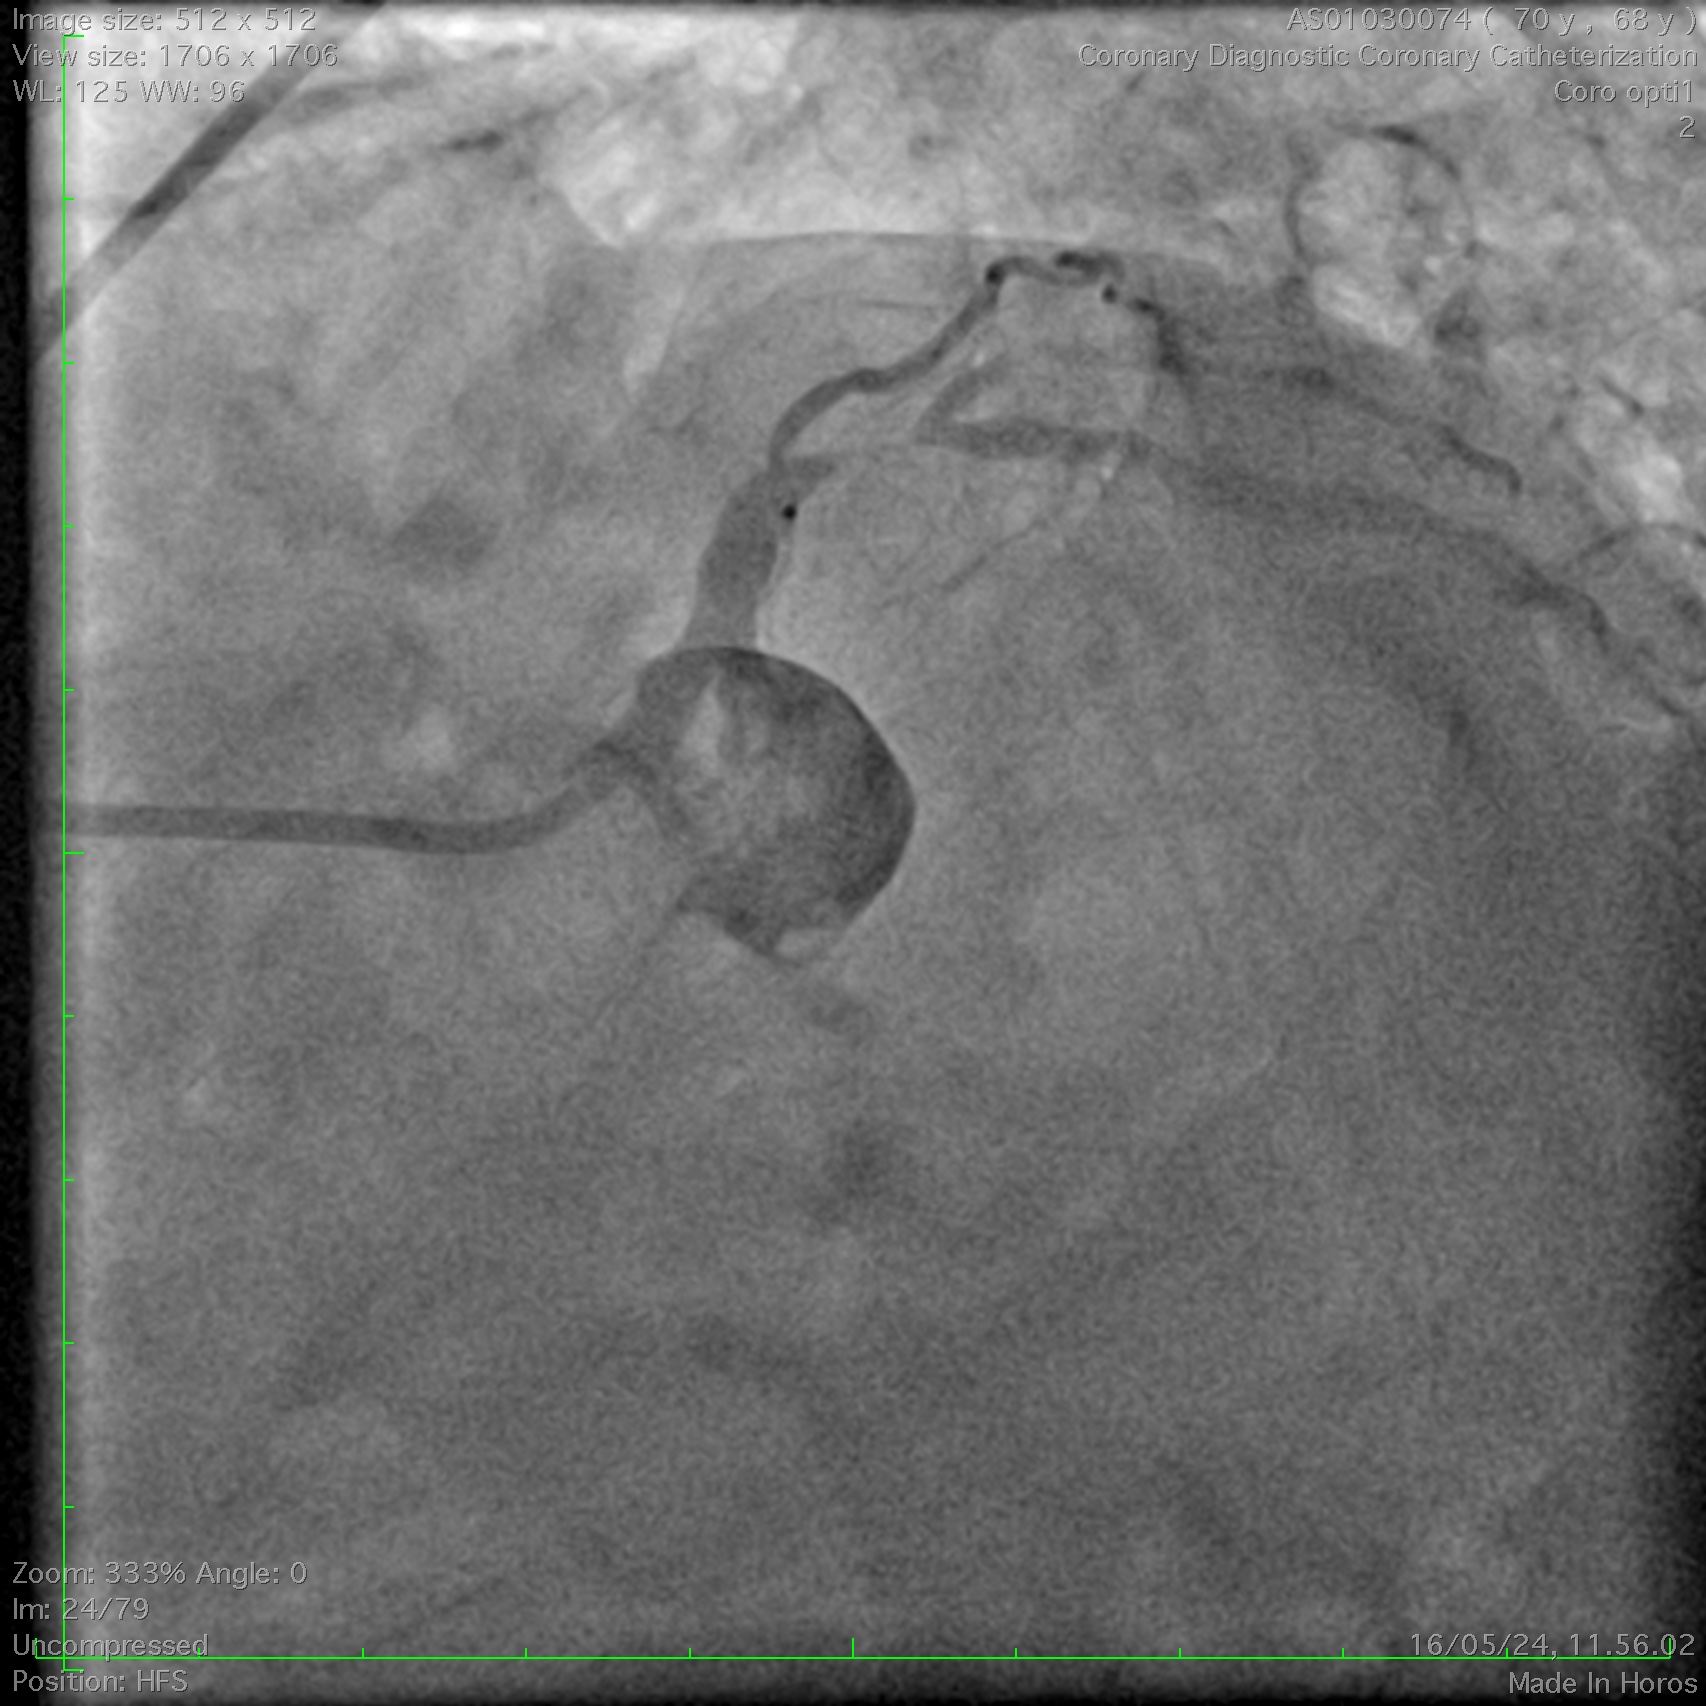

Coronary angiography demonstrated a right-dominant system with significant ostial LCx stenosis and a blunt ostial LAD chronic total occlusion, with a J-CTO score of 4. The RCA showed mild coronary disease and supplied collateral flow to the LAD territory, graded as Werner CC2.